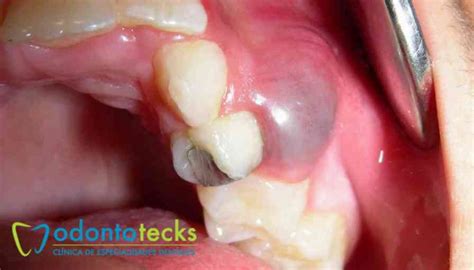

Un quiste es un saco biológico que se forma en nuestro organismo y que puede contener líquido, aire o cualquier otro tipo de materia orgánica. Profesionalmente, los quistes en los dientes reciben el nombre de quistes odontogénicos. Un quiste dental es una pequeña bolsa llena de líquido, aire, o células que se forma en relación con un diente. Por lo general, se detectan en radiografías de rutina y, aunque suelen ser benignos, es importante tratarlos para evitar complicaciones.

Se trata de unas cavidades que suelen ser una extensión de una infección que se ha producido en los dientes o huesos adyacentes. En su interior, están formados por pus, que es un material que puede estar en estado semisólido o también en estado líquido.

- Puede aparecer una protuberancia semiblanda en la encía cuyo interior está formado por pus.